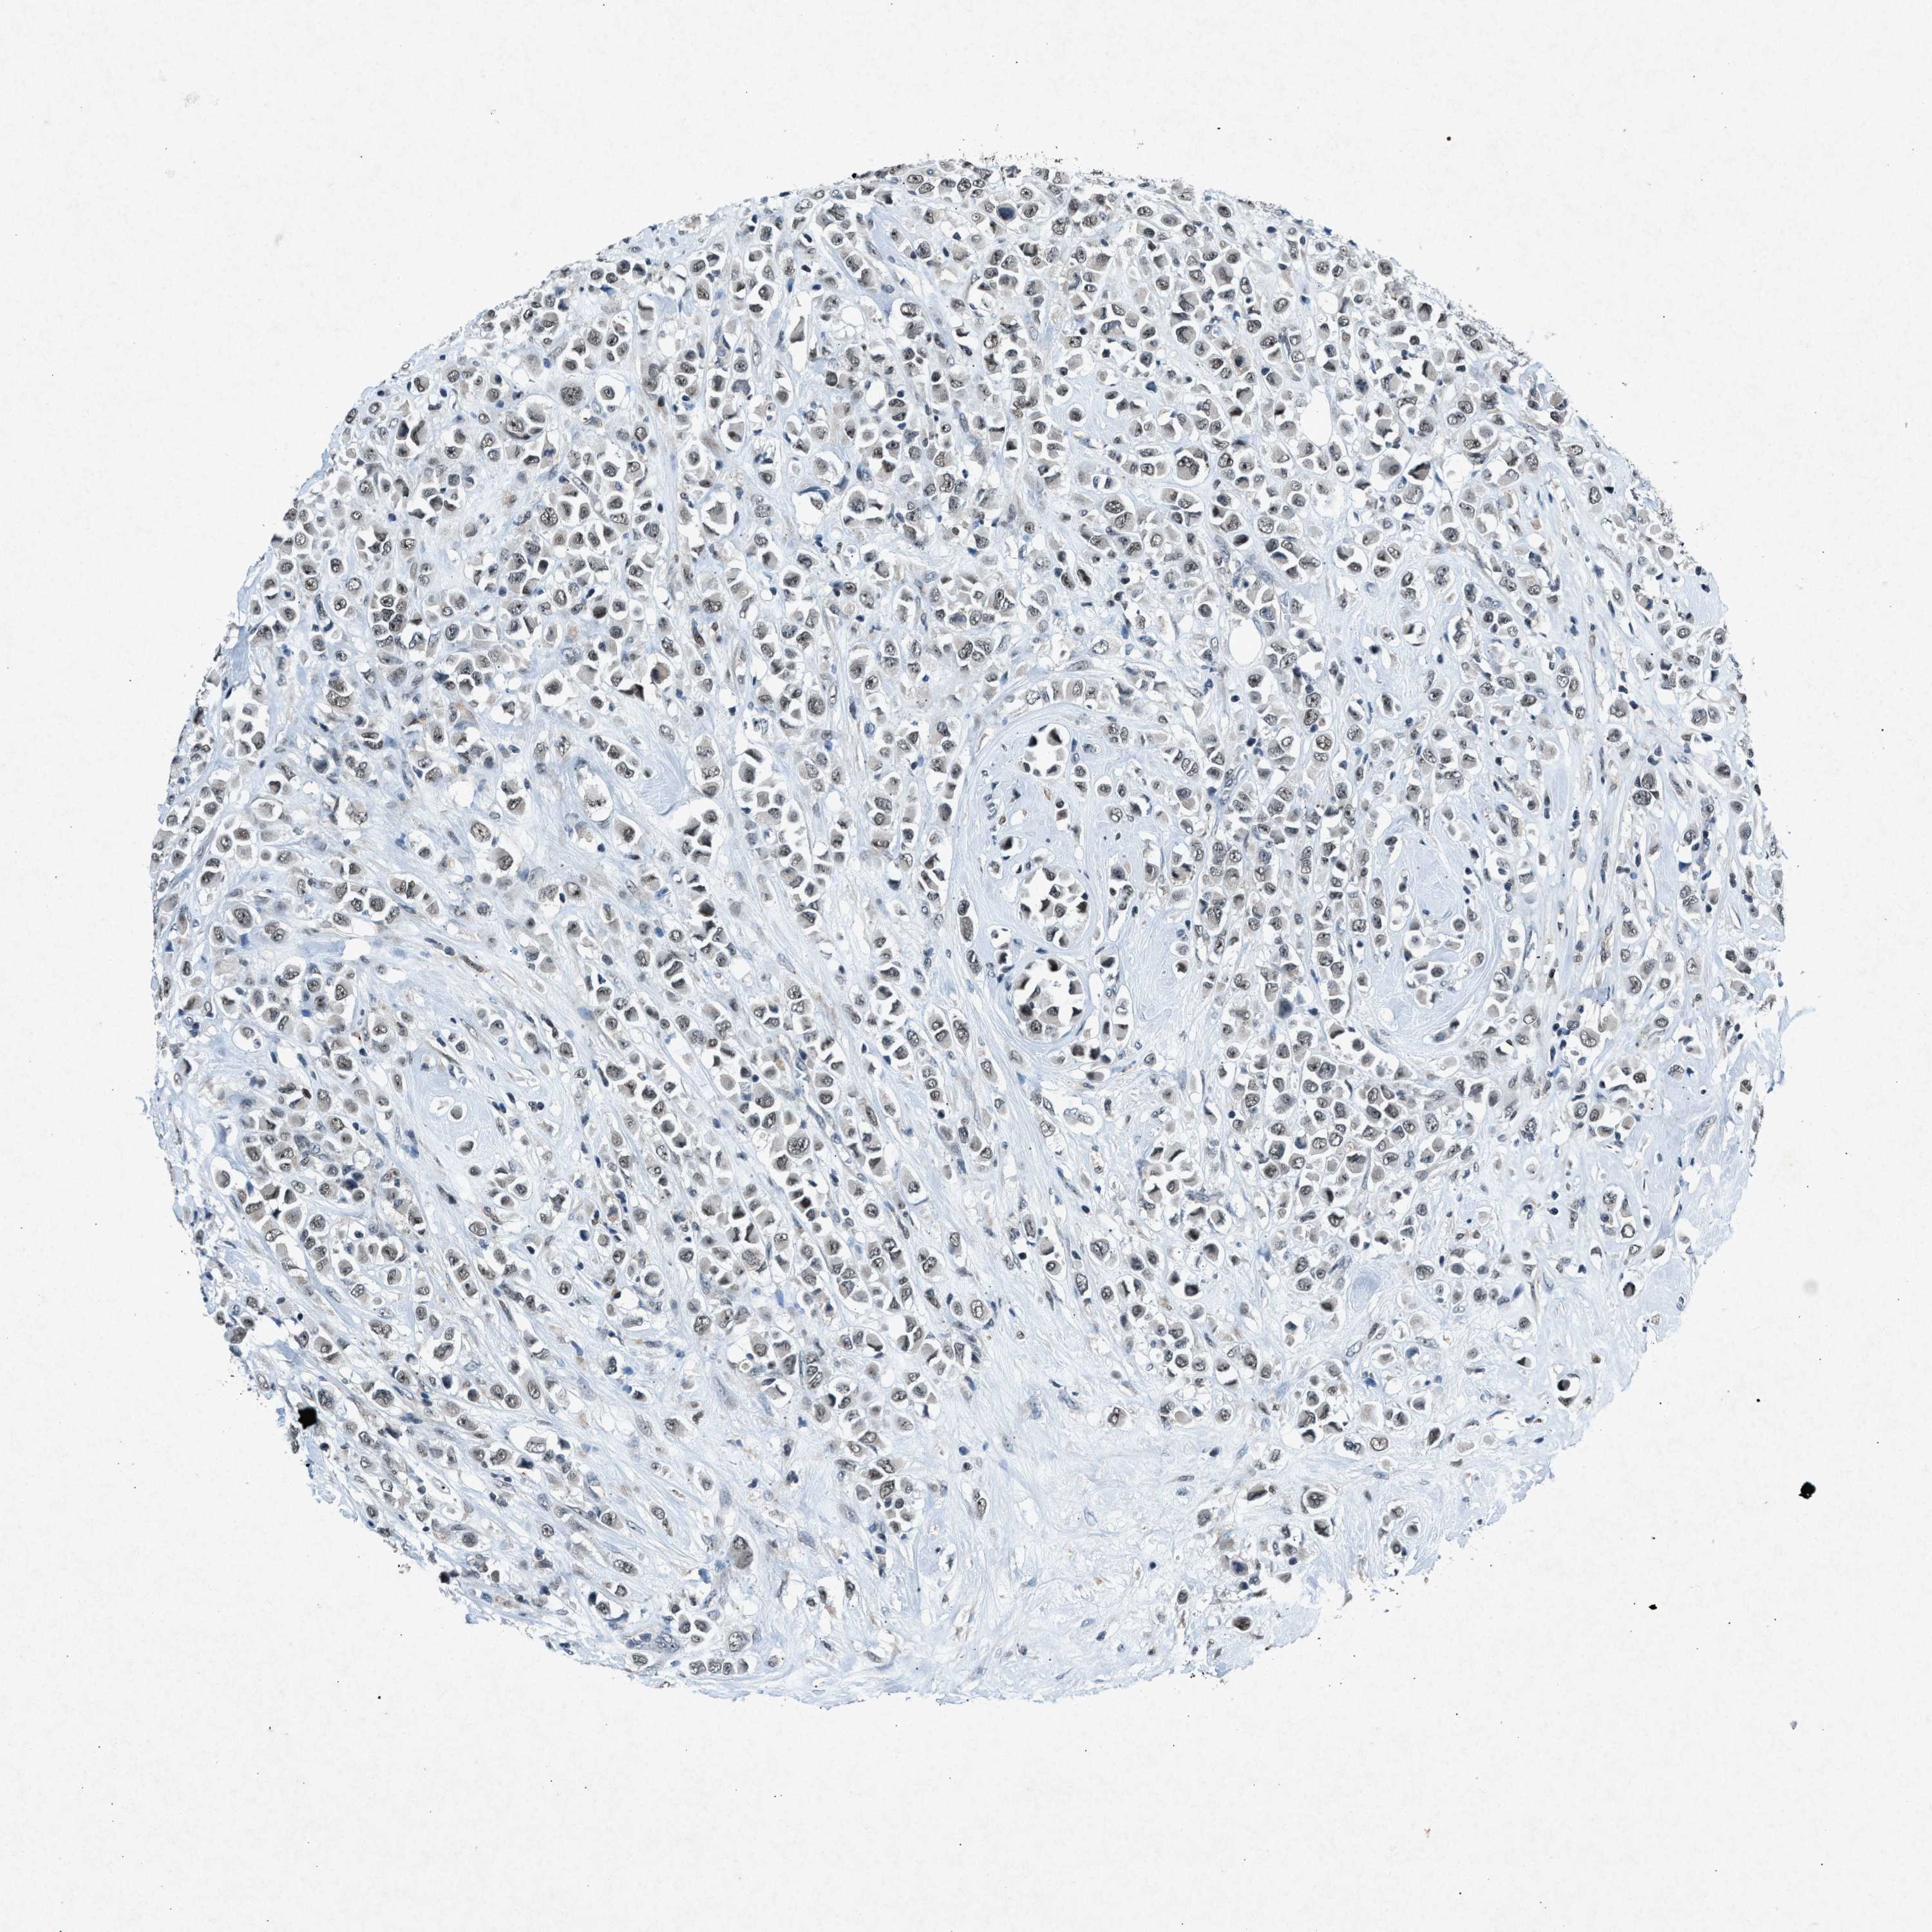

BRCA TCGA BRCA VALIDATION PROTEIN EXPRESSION